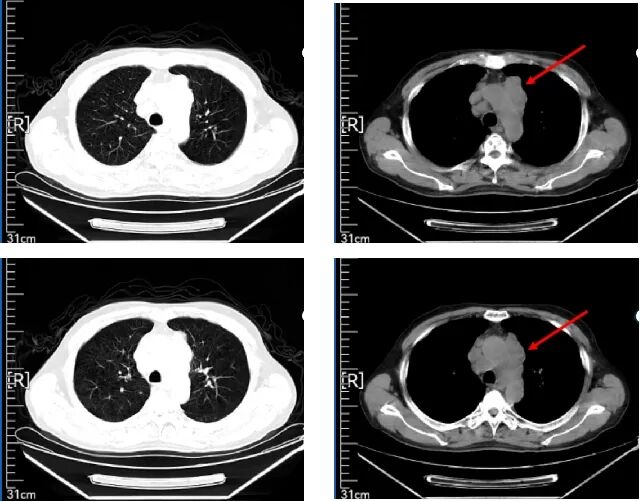

2021.12.02 肺部CT显示:双侧胸廓对称,左肺上叶可见软组织密度肿块影,大小约3.6*3.0cm,边界不清,密度不均,肿块与左肺动脉分界不清。左肺门及纵隔内可见多发增大淋巴结影,大者位于主支气管前方,短径约1.7cm,左肺上叶舌段、下叶后基底段可见小结节影(im3-42),大者径约0.3cm,心脏不大。心包腔内可见液体密度影。双侧胸膜未见明显增厚,胸腔未见明显液体密度影。

诊断意见:左肺上叶软组织肿块,考虑恶性,请结合临床或增强扫描;左肺门及纵膈多发增大淋巴结,考虑MT;左肺小结节,建议定期复查;心包职液。

肺部CT

2021.12.02-2022.03.08 给予派安普利单抗200mg d1+依托泊苷0.1g d2-6+顺铂 120mg d2治疗4周期后,行肺部CT检查结果显示,病灶较2021.12.02片有明显缩小。派安普利单抗200mg d1+依托泊苷0.1g d2-6+顺铂 120mg d2治疗4周期疗效评价为PR。

疗效评估